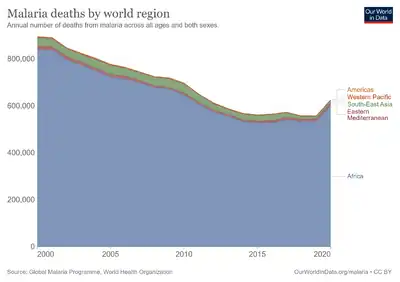

Species of Plasmodium are distributed globally wherever suitable hosts are found. Insect hosts are most frequently mosquitoes of the genera Culex and Anopheles. Vertebrate hosts include reptiles, birds, and mammals. Plasmodium parasites were first identified in the late 19th century by Charles Laveran. Over the course of the 20th century, many other species were discovered in various hosts and classified, including five species that regularly infect humans: P. vivax, P. falciparum, P. malariae, P. ovale, and P. knowlesi. P. falciparum is by far the most lethal in humans, resulting in hundreds of thousands of deaths per year. A number of drugs have been developed to treat Plasmodium infection; however, the parasites have evolved resistance to each drug developed.